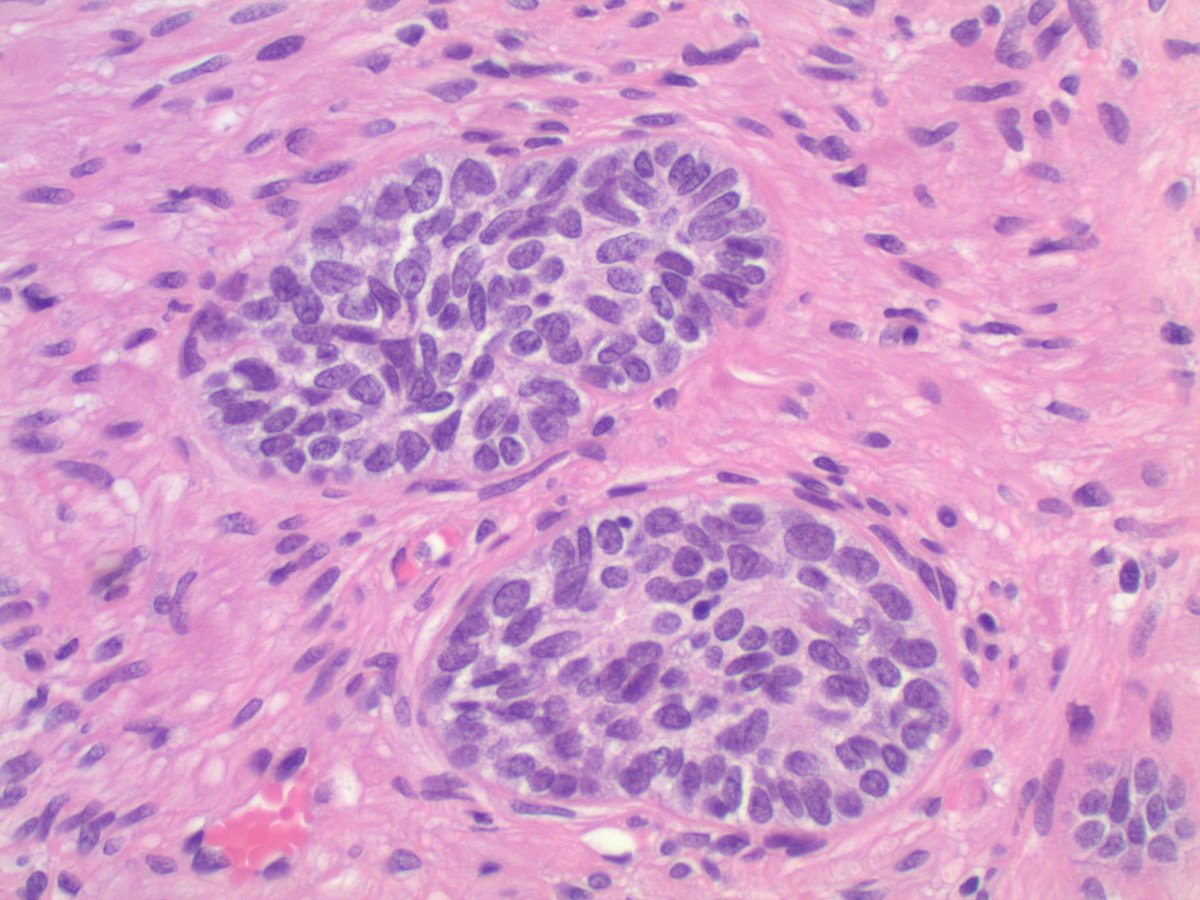

4.3 cm renal mass confined to kidney, tumor cells are predominantly with proliferative, tubular pattern 🎨 CK7 positive (strong, diffuse) 🎨 CD117 negative Thoughts? Sean R Williamson MD Kiril_T_Can Michelle_Hirsch (Donovan) Priya Rao, MD Ankur Sangoi

Kidney, young F adult #gupath Dr. Luca Olaleke Folaranmi Aurélien Morini, MD, MSc 🇫🇷🇪🇺💙💛 Celina Stayerman MD 🔻Nusrat Zahra🔻🇵🇸 @miss_me1986 Gonzalo De Toro Tristan Rutland MBBS FRCPA IFCAP Anandi Lobo, MD Sumanta Das Lorand Kis Erik Kouba bansar Carlos Miguel Ruiz Carlos Nieves Padma Priya J Susan Prendeville @AkgulMd Ankur Sangoi Barry McGinn